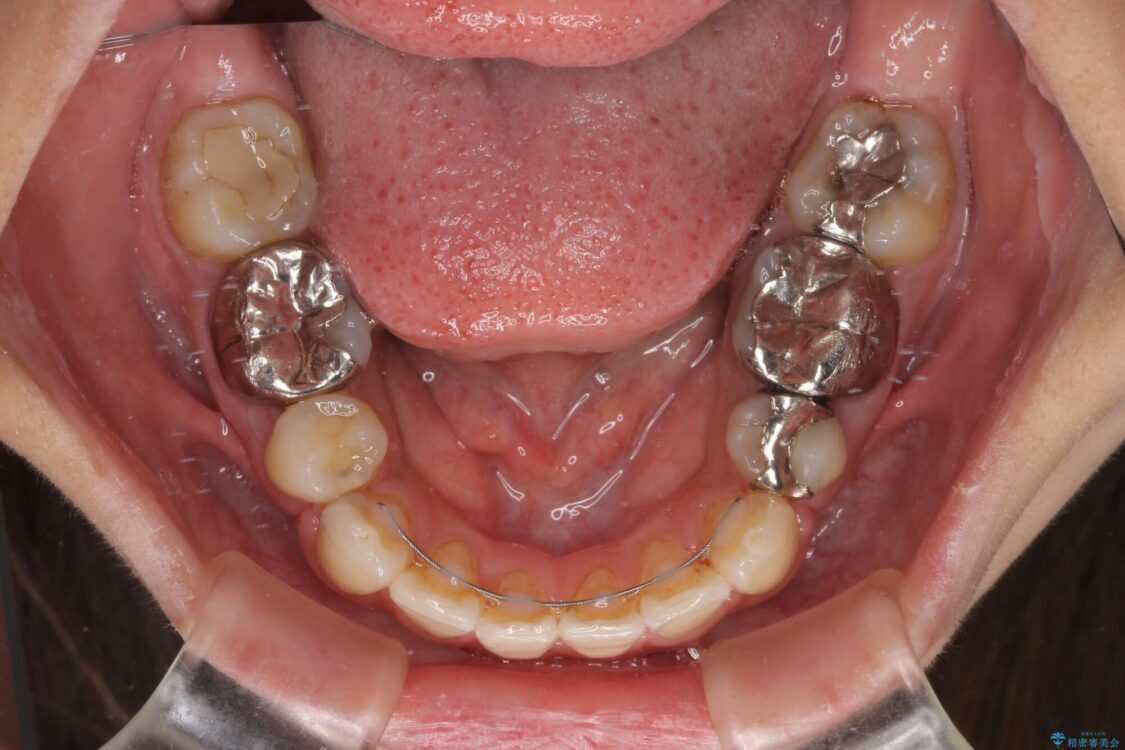

治療前

• デコボコと口元の突出感 ハーフリンガルでの抜歯矯正 治療前画像